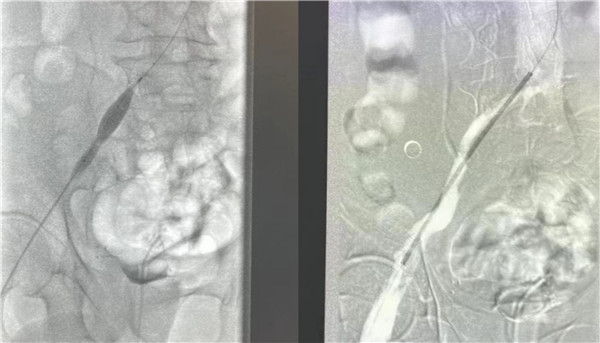

高大爷入院后立刻开启绿色通道,普外科血管介入团队放弃假期休息,当天急诊为他进行了介入手术治疗。为了防止肺栓塞的发生,首先为高大爷进行下腔静脉滤器的植入,与此同时造影显示患者左下肢血管内布满血栓,使用AcoStream血栓抽吸系统为患者清除血管内的血栓,高大爷还存在左侧“髂静脉压迫综合征”立刻完善方案,为他进行球囊扩张,支架植入,在保证患者的安全前提下,采用“一站式”解决方案,一次性为高大爷从病根上解决诱发血栓的原因并治疗了血栓,即刻效果显著,高大爷下肢大腿腿围术前43厘米,术后即刻41.5厘米,术后第一天41厘米,小腿腿围术前34厘米,术后即刻32厘米,术后第一天31厘米。同时也避免可能的PTS发生。介入手术创伤小,仅有一个穿刺点,患者术后恢复快,大大的提高了患者的就医感受,并且为患者节省了费用。

下肢深静脉血栓患者术前造影

球囊扩张